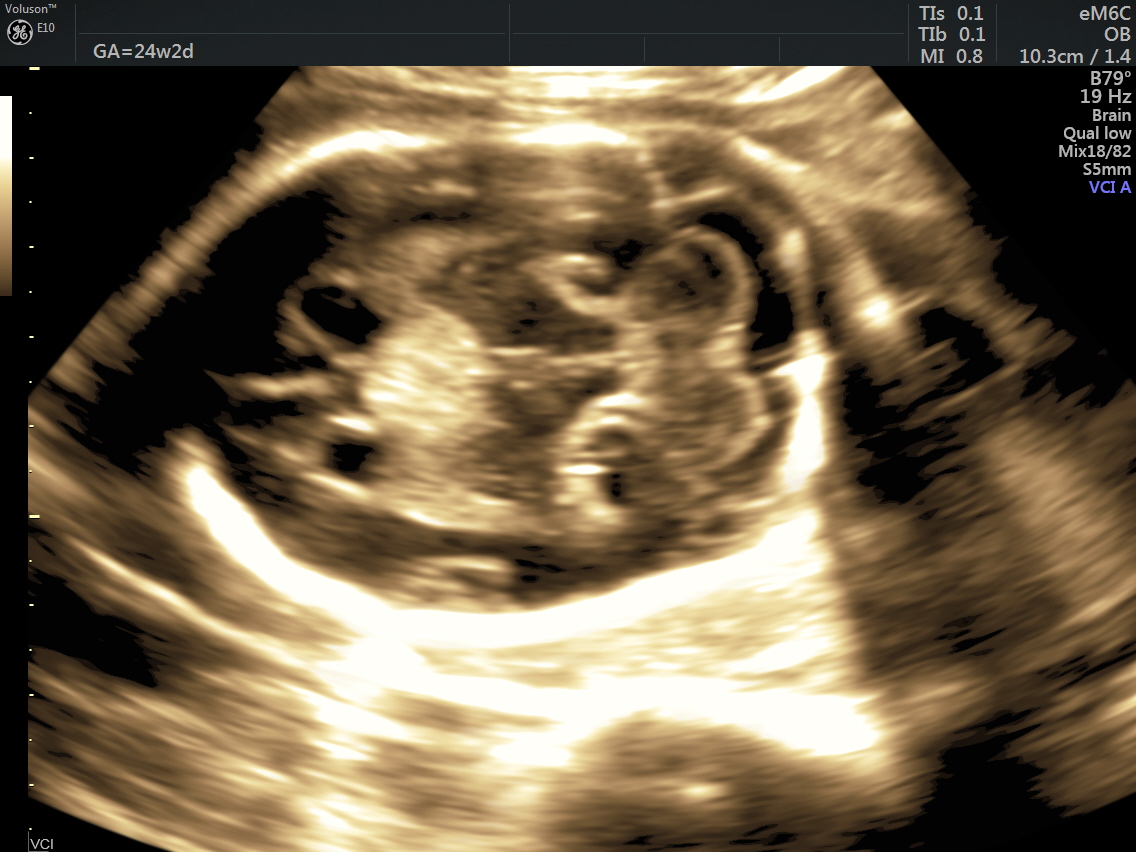

Her BPD ( 6.5 % tile) and HC ( 7 % tile) were less than 10 % tile. Mild ventriculomegaly was seen. ( 11.34 % tile).

A careful look at the 3rd ventricle shows a solid mass.

Some reconstructed images are given below.